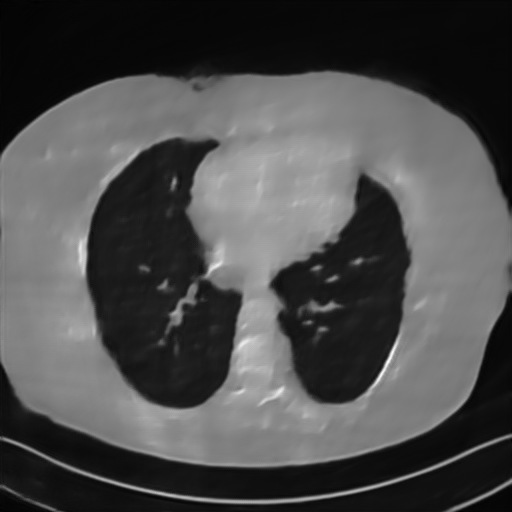

Fig. 4 presents the reconstruction results and residual images obtained by different methods for limited-angle reconstruction. As can be seen, the learning-based methods outperform the direct method and TV model, which exhibit serious artifacts in the missing angle region. Although the denoiser introduced by the FBP-Unet can somehow deal with the noises, the result still presents obvious artifacts. Compared to the SIPID, PD-net and FSR-nets, our LRIP-net1/2 can better preserve the image details and edges with less information left in the residual images. Thus, both the quantitative and qualitative results confirm that the low-to-high double-resolution strategy can improve the reconstruction accuracy for the limited-angle reconstruction problem.

We observe that the low-resolution image prior plays an important role in our method. More specifically, we compare the results of our LRIP-net with respect to different low-resolution priors, which are obtained by down-sampling rate of 1/2, 1/4, and 1/8, respectively. As can be seen in Table III, the best reconstruction results are obtained with the image prior reconstructed by the down-sampling rate of for 150∘, 120∘ and 90∘ limited-angle reconstruction. The visual comparison based on different image priors are also provided in Fig. 5, where obviously less artifacts are left in the reconstruction image by LRIP-net1/8. By comparing the running time, it is easy to see that the smaller the low-resolution image prior, the faster the LRIP-net works.